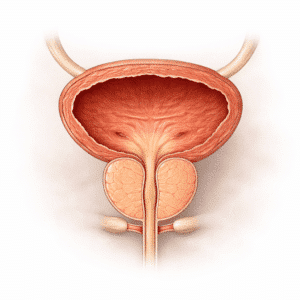

Bladder & Urinary Infections

What Are Bladder & Urinary Infections? Bladder infections and urinary…

Urinary Incontinence

What is Urinary Incontinence? Urinary incontinence is the unintentional loss…